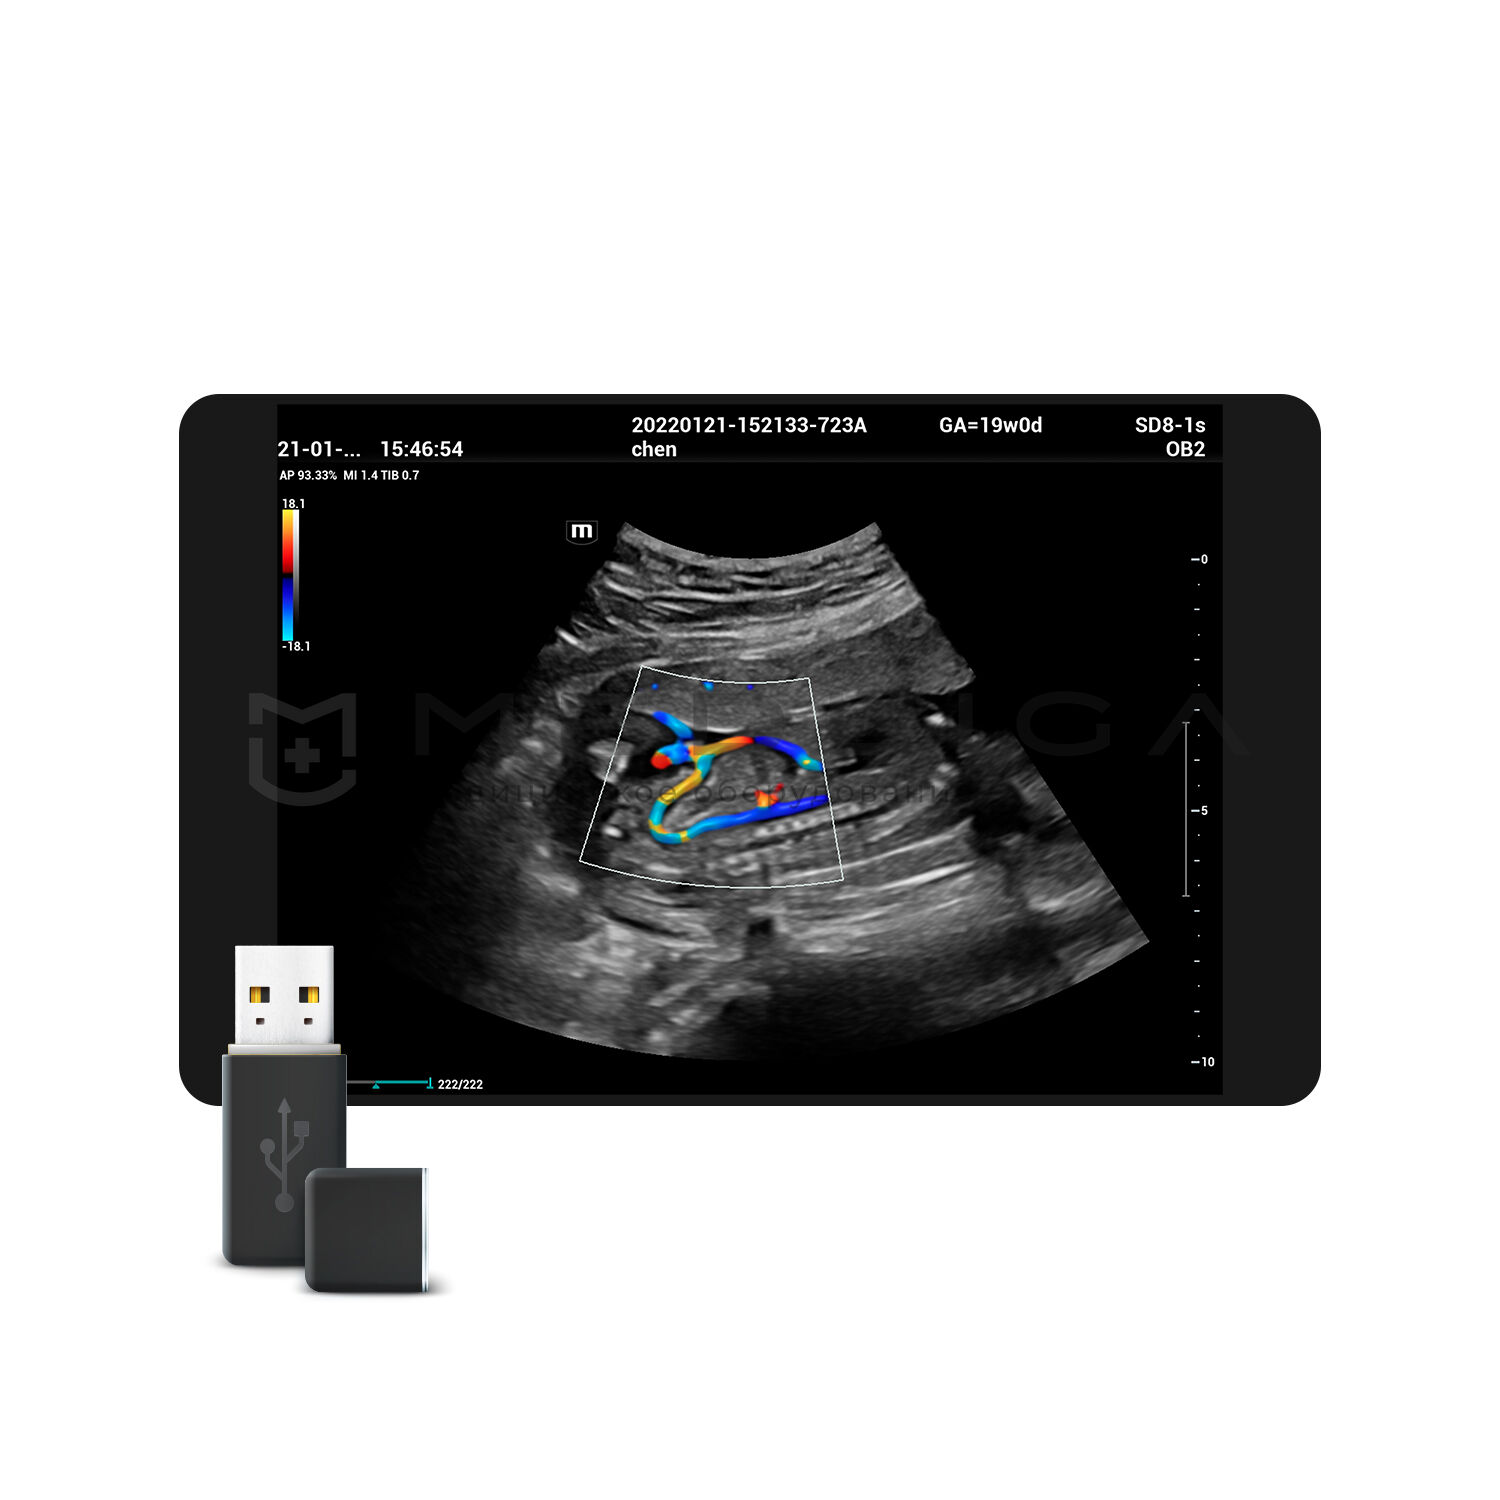

Для эхокардиографии используются секторные фазированные датчики и дополнительные допплеровские режимы с целью исследования сердечной деятельности.